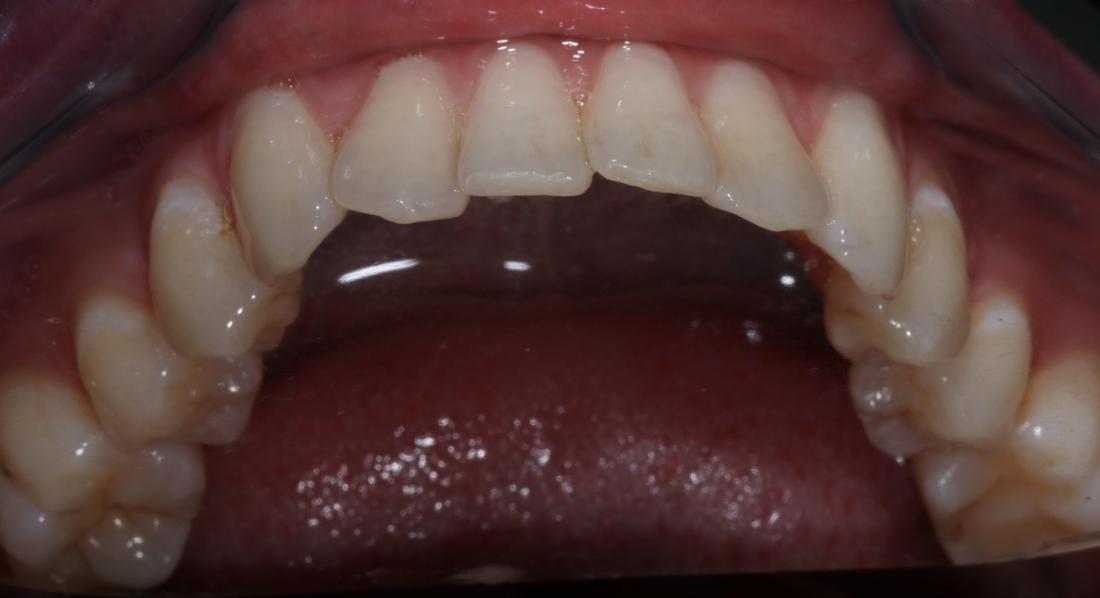

This dental patient arrived at our dental office in Goffstown requesting a straighter smile. We knew this patient would be a perfect candidate for Invisalign clear aligner treatment. After a short consultation, our expert dental team got to work on the Invisalign process and in a few short months, this patient was able to smile with confidence.

One of the first priorities was getting my teeth straightened. I was surprised when I was offered a solution right there at my primary dentist office and did not have to travel to a specialist. I recently got my brackets removed after about a year and the results are AMAZING! The best part was the level of care I received along the way. Any time I had a question or concern it was addressed immediately and they always made time for me to stop by. They have been exceptional with the level of patient care they provide!